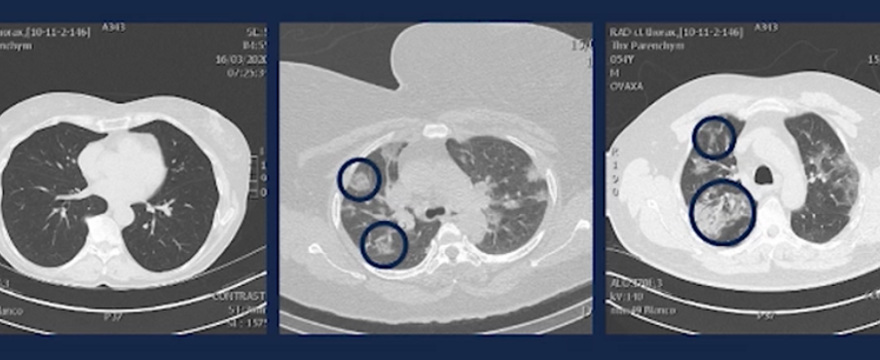

Dotychczas uważano, że koronawirus największe spustoszenie sieje wśród ludzi starszych. Tymczasem nawet młodzi ludzie w wieku 20-50 lat, muszą na siebie bardzo uważać. Mimo, że koronawirus w tej populacji wiekowej nie powoduje tak dużej śmiertelności, sieje on ogromne spustoszenie w płucach.

Lekarz przytoczył historie wielu pacjentów, którzy trafiają teraz na oddziały wirusologiczne. To młodzi ludzie, nieobciążeni dodatkowymi chorobami, którzy przez pewien czas chorowali - najpierw około tygodnia w domu z objawami grypopodobnymi i gorączką, a gdy poczuli się lepiej zaczęli wychodzić na zewnątrz.

Po dwóch dniach zazwyczaj trafiali już na oddział z dusznościami i kaszlem – a skany ich płuc były przerażające!